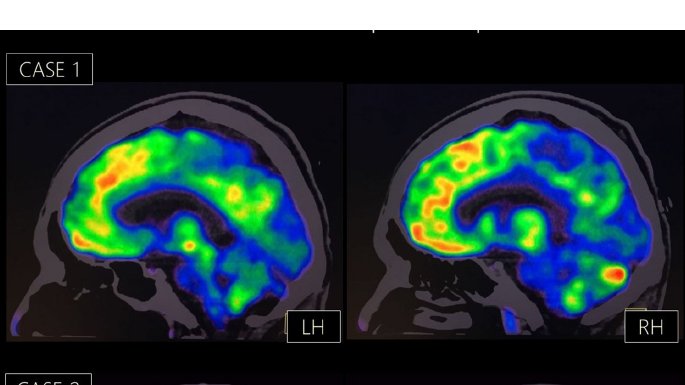

4/5 He would state repeatedly: “I do not have feelings because I am dead.” He said that he had a “right-sided” heart & that it had stopped. A brain 18F-FDG PET study revealed prominent hypometabolism in the right occipito-parietal cortex,more accentuated in the right hemisphere.